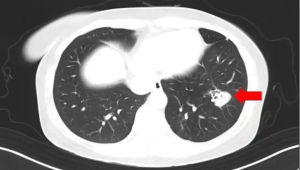

随着病情的加重,他不得不前往医院进行检查。医生为他做了一系列详细的检查,包括胸部CT等,最终发现他的肺部出现了霉菌感染,也就是肺部发霉的情况。经过进一步的询问和分析,医生判断这很可能是在山区民宿居住期间,由于环境潮湿、通风不良,他吸入了大量带有霉菌孢子的空气,从而导致肺部感染。在假期里,人们通常会因为忙碌于游玩或者休息,而忽视了居住环境的卫生和通风情况。像这种潮湿、通风差的环境,非常容易滋生霉菌。霉菌孢子一旦被人体吸入,就有可能在呼吸道和肺部大量繁殖,从而引发感染。

肺部发霉可不是小事,它会严重影响肺部的正常功能,导致呼吸困难、咳嗽、发热等症状。如果不及时治疗,还可能引发更严重的并发症,甚至危及生命。对于这位患者来说,他的病情发现还算及时,医生根据他的具体情况制定了详细的治疗方案,包括使用抗真菌药物、进行呼吸支持等。在经过一段时间的治疗后,他的病情逐渐得到了控制,体温也恢复了正常,咳嗽等症状也明显减轻。